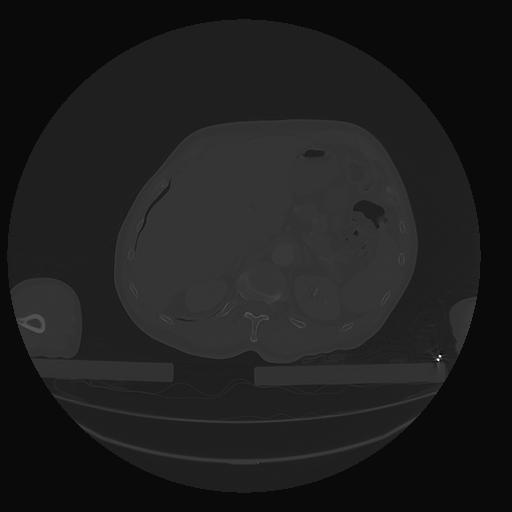

31 PULMON,CE,Vol,1.0,PULMON,,